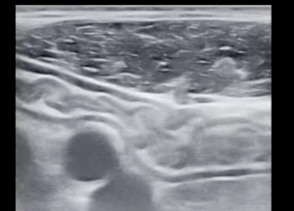

L’échographie permet la visualisation de l’ensemble du cadre colique, de la dernière anse iléale et des anses grêles, par balayage de l’épigastre jusqu’au pelvis. Les points analysés sont l’épaisseur pariétale (fig. 1), le signal doppler, les anomalies de la graisse mésentérique, la stratification pariétale, le péristaltisme, la présence d’ulcérations, d’adénopathies ou de complications (fistule, abcès, sténose ou épanchement intra-abdominal [fig. 2]). L’examen échographique permet de localiser ces éléments sémiologiques et de préciser la longueur de l’atteinte, le cas échéant.3